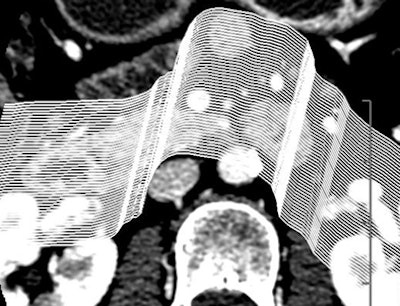

Certainly imaging-based diagnosis of the cysts has its limitations. For one thing, MDCT can diagnose six different pancreatic lesion types, including side branch intraductal papillary mucinous neoplasms (IPMNs), serous microcystic adenomas, epithelial cysts, mucinous cystic neoplasms, lymphatic cysts, and cystic islet cell tumors. But it can't always tell them apart.

Some lesion types look the same at CT, with overlapping appearance occurring, for example, between a mucinous cystic neoplasm and a thin-walled simple cyst that has no risk of malignancy. And mucinous cystic neoplasms are indistinguishable from benign epithelial cysts.

"There's no way to distinguish them, so by the time your cyst has exceeded 4 cm, you've pretty much bought yourself a needle aspiration," Jeffrey said. Esophageal EUS-guided fine-needle aspiration is the key to differentiating these small cyst types and in fact the way to evaluate most lesions larger than 3 cm in diameter.

Worrisome features for malignancy are solid tissue within the cyst, obstruction of the main pancreatic duct ≥ 1 cm or the common bile duct, regional lymphadenopathy, or interval enlargement of a lesion, Jeffrey said.